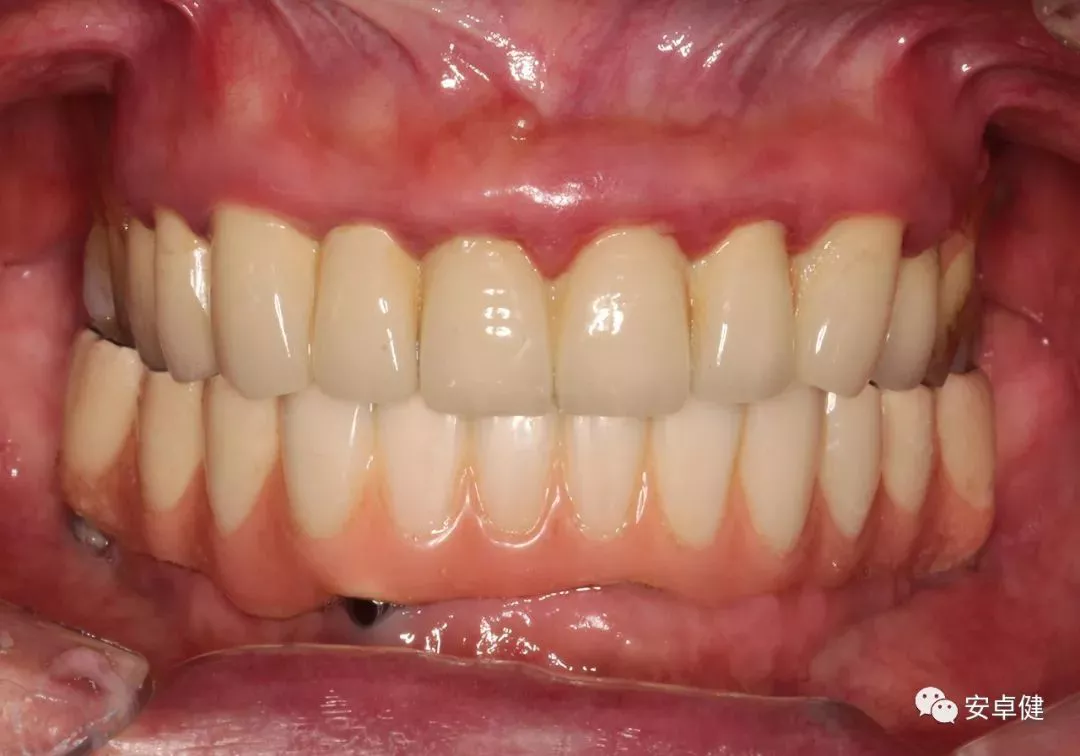

最终修复后8个月

戴牙后8个月复诊正面咬合照

戴牙后8个月复诊正面微张照

戴牙后8个月复诊合面照

• 随访可见患者口腔卫生状况可,牙龈无红肿;

• 下颌修复体状态良好,无修复体机械并发症;

• 种植体基台稳定性良好,无松动;

• 种植体无松动,周围无红肿、溢脓及疼痛表现;

• 正中、前伸及侧方咬合检查可见咬合印记分布均匀,咬合关系良好;

• 患者反映日常使用良好,舒适性佳,满意度高。

术后采取即刻义齿修复,可即时满足患者日常咀嚼功能及美观的需求。术后4个月,种植体周软硬组织愈合稳定后,再次取模制作第二副临时过渡义齿,以期进一步改善美观、稳定患者的咬合关系。由于疫情原因,患者最终修复延迟了半年以上。最终修复体参照第二副临时义齿的外形及咬合关系,患者无不适期。

完成最终修复体及其后8个月的随访,可见种植体周牙槽骨稳定,口内种植体周围软组织无明显炎症,在美观和功能方面都取得了较为满意的结果。该病例获得了较为稳定的临床效果,可为无牙颌患者的临床诊疗工作提供一定的参考。故临床中针对符合种植适应证的无牙颌患者,可结合患者综合情况,考虑为其制定个性化全口固定式种植义齿的修复方案。